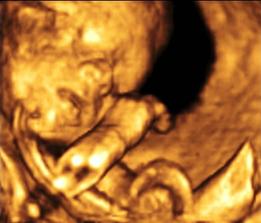

Ako nám to ide...